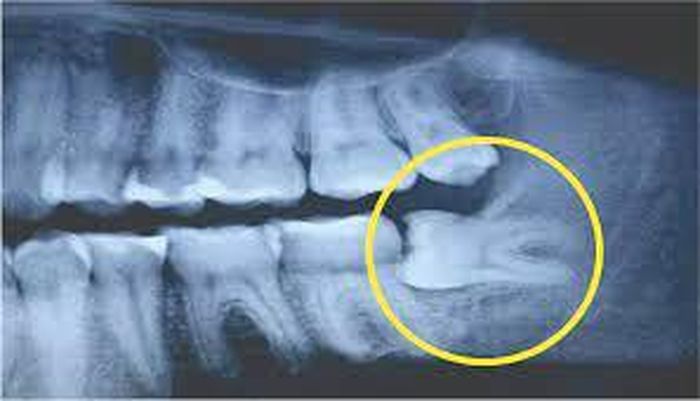

Sau khi có kết quả chụp X-Quang, bác sĩ chẩn đoán do 1 răng khôn của Lin mọc ngầm và lệch nên mới dẫn đến tình trạng đau nhức. 3 chiếc răng khôn khác cũng bị ảnh hưởng.